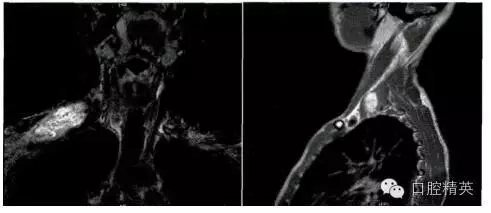

影像學檢查:頸部MRI(平掃+增強)提示右肩部鎖骨上區(qū)皮下軟組織內(nèi)一巨大腫物,大小約6.1 cm×2.8 cm,其內(nèi)信號不均勻,T1W1為等信號,T2W2為混雜高信號,考慮神經(jīng)源性腫瘤,右側(cè)臂叢神經(jīng)可疑受累(圖1)。臨床初步診斷為“右頸神經(jīng)鞘瘤”。

圖1.頸部MRI示右鎖骨上區(qū)皮下軟組織內(nèi)一巨大腫物